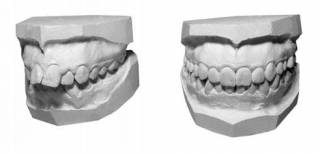

Модели зубов в ортодонтии получают при обработке слепков, которые являются результатом проекции зубов на слепочные массы. В некоторых случаях приходится делать и компьютерную обработку получаемых моделей.